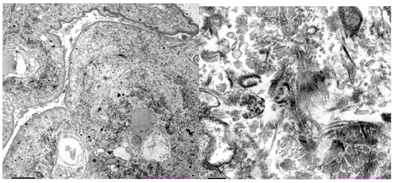

电镜检查(图2):镜下检测到1个肾小球。毛细血管内皮细胞明显空泡变性,个别管腔内可见红细胞,无明显内皮细胞增生,毛细血管襻部分受压。肾小囊壁层增厚、分层,壁层细胞空泡变性,无明显增生。基底膜:节段性增厚,厚度300~700 nm,节段性皱缩。脏层上皮细胞:上皮细胞肿胀,空泡变性。足突融合情况观察不清。系膜区:系膜细胞和基质增生。未见电子致密物沉积。系膜区及基底膜内侧可见大量规律排列有横纹的Ⅲ型胶原纤维。肾小管-间质:部分肾小管萎缩。肾间质淋巴、单个核细胞浸润伴胶原纤维增生。肾间质血管:个别毛细血管管腔内见红细胞。免疫组化(图3):肾小球Ⅲ型胶原(+),Ⅰ型胶原(-)。符合Ⅲ型胶原肾病。

该病肾脏病理的主要表现为系膜区明显增宽,以系膜基质增生为主,系膜细胞一般无增生,重度增生时可表现为结节状硬化,形似糖尿病肾病K-W结节形态;毛细血管基底膜弥漫增厚,双轨征形成;内皮下和系膜区大量弱PAS阳性物质沉积,常使毛细血管腔受压闭塞。免疫荧光常阴性,偶见IgM、C3在系膜区、血管袢局灶节段沉积。确诊主要依靠电镜及免疫组化检查。电镜下可见系膜区增宽、基质增加、内皮下间隙增宽。可见电子致密的、散在或束状聚集的、直径43~65 nm、规律排列有横纹的纤维状物,在增宽的系膜区、系膜旁区及内皮下积聚。通过免疫组织化学,可明确胶原纤维是单一的Ⅲ型胶原纤维。